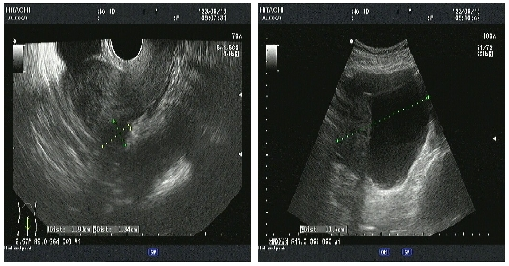

04、**女士,50岁

于2023年6月13日在邯郸仁泰东区体检,子宫附件彩超检查提示:盆腔内不规则囊实性包块,大小约21*11*10cm,以囊性为主,内见多个分隔,部分内透声差,CDFI:实性部分可见血流信号。2023年6月13日首次回访,通知客户到三甲医院进一步检查。2023年7月18日跟踪回访,客户告知,已在邯郸市中心医院东区完成肿瘤切除手术,术后恢复良好。